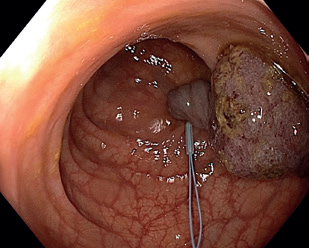

Obr. 12 Objemná léze v žaludku označená koagulačními body.Endoskopická submukózní disekce má celou řadu modifikací, za zmínku stojí zejména metoda „pocket creation”, kde se z malé incize postupně disekuje pod lézí submukózní tunel – „kapsa” – a po disekci celé léze je následně dokončena slizniční incize. Tato metoda je vhodná například pro nestabilní polohy endoskopu. Vznikly i další modifikace s cílem techniku zjednodušit, například „precut EMR” (EMR‑P) a metoda hybridní ESD („simplified ESD”, S‑ESD). Při EMR‑P je provedena cirkulární incize jako při ESD, poté je do incize vložena klička a léze je resekována. Při S‑ESD je po cirkulární incizi provedena částečná disekce cirkulárně směrem k centru léze, která je následně resekována kličkou.

Obr. 13 Částečně disekovaná léze.Endoskopická transmurální resekce (full‑thickness resection, FTR) představuje jistou formu evropské „odpovědi” na japonskou metodu ESD. Ostatní metody (zejm. EMR a ESD) jsou limitovány na povrchové vrstvy střevní stěny, v některých případech toto ale není dostatečné. Příkladem může být výrazná fibróza pod lézí znemožňující resekci, popřípadě léze vycházející z hlubších vrstev stěny. FTR umožňuje provést resekci celé šíře střevní stěny, a to bez vytvoření volné perforace. Původní nástroje byly velmi objemné, a tedy značně komplikovaly manévrovací schopnost endoskopu, toto se změnilo s představením OTSC klipů (over‑the‑scope‑clip). S jejich použitím bylo vyvinuto zařízení na FTR (FTRD – FTR device). Jedná se o jednokrokový resekční přístroj kombinující modifikovaný OTSC klip nasazený na průhledný nástavec s předinstalovanou kličkou.